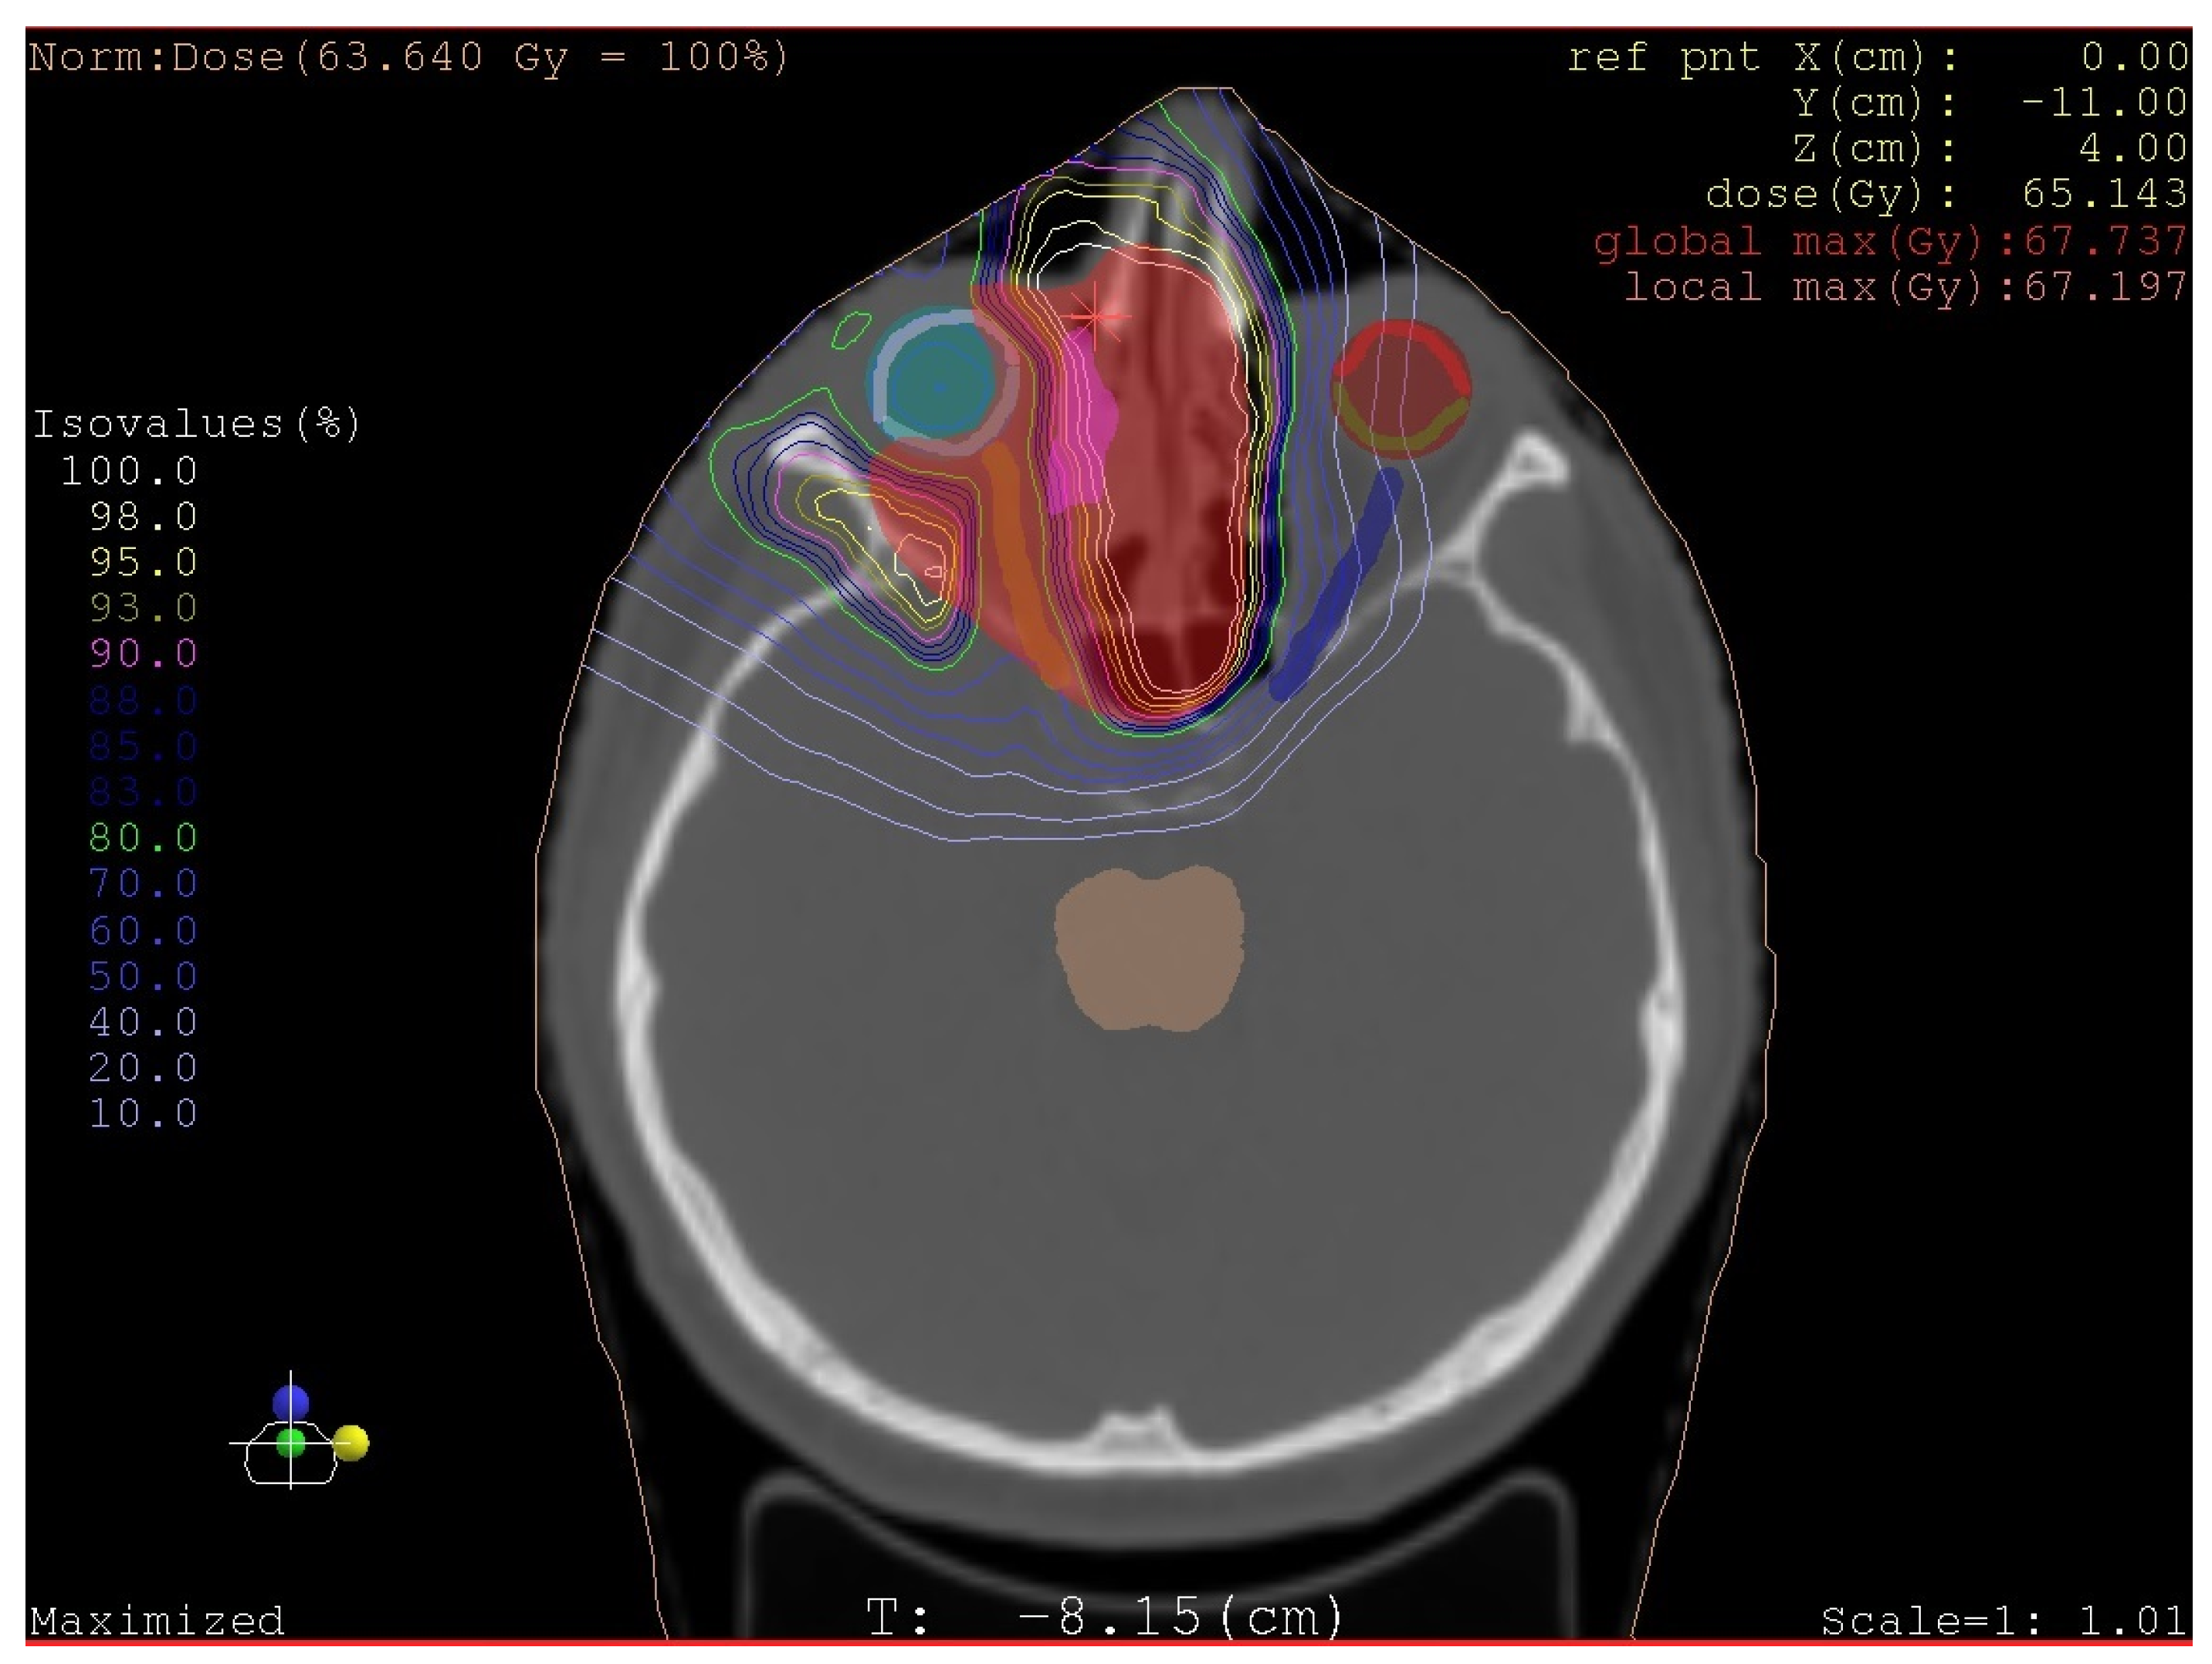

- Radiotherapy: beam therapy (photon, proton, or isotope) depends on staging, including grading, histological type of sarcoma, and the radicality of surgery when performed.